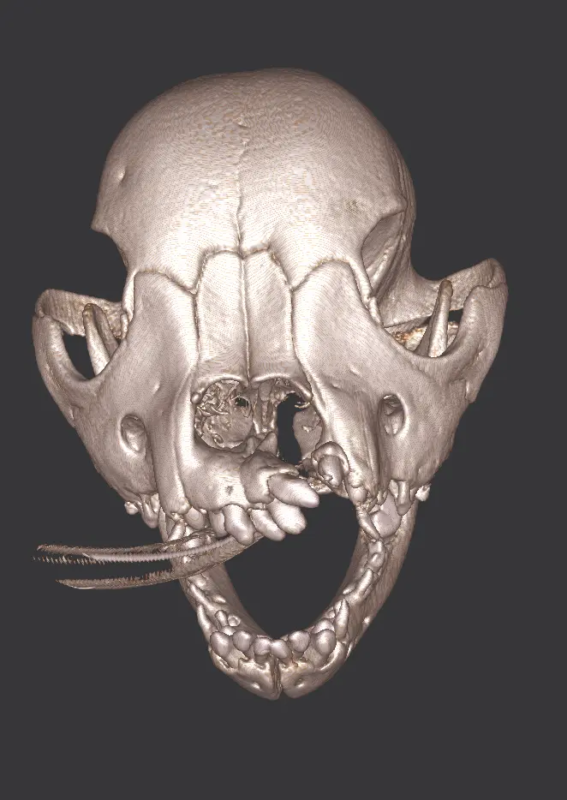

Cone Beam Computed Tomography

The Center now provides advanced imaging via cone beam CT. Cone beam CT is excellent for visualization of bony structures of the skull, nasal cavity, teeth, and ears. Cone beam CT is especially helpful for diagnosing dental disease and evaluation of jaw fractures. It can also be useful for evaluating the sinuses and tympanic bulla. Cone beam CT can be used in conjunction with nasal biopsy and culture to evaluate nasal discharge whether chronic or acute.

Tumors of the Maxilla, Mandible and Facial Area

Oral tumors are very common in dogs and cats. Many of these tumors can be successfully removed with surgery. Benign tumors can be cured with surgery alone, and malignant tumors can be treated with surgery and some combination of radiation or chemotherapy. In many cases oral tumors cause a great degree of discomfort or are bleeding and need to be removed to allow your pet to be more comfortable.

Repair of Maxillofacial Fracture

Pets can be involved in trauma that can cause fractures to their head, teeth, and jaw bones. Correctly repairing these fractures is extremely important for your pet to have normal function of their mouth. If a jaw fracture is allowed to heal in an abnormal position, your pet may have great difficulty chewing and can be in significant pain. Many fractures can be successfully treated with minimally invasive oral procedures, but more complicated cases may require bone plating techniques. The Center offers cone beam CT imaging which provides extremely detailed images of the bones of the head and skull. Advanced imaging with CBCT facilitates selection of the best surgical technique to get your pet back to eating and comfort as soon as possible.